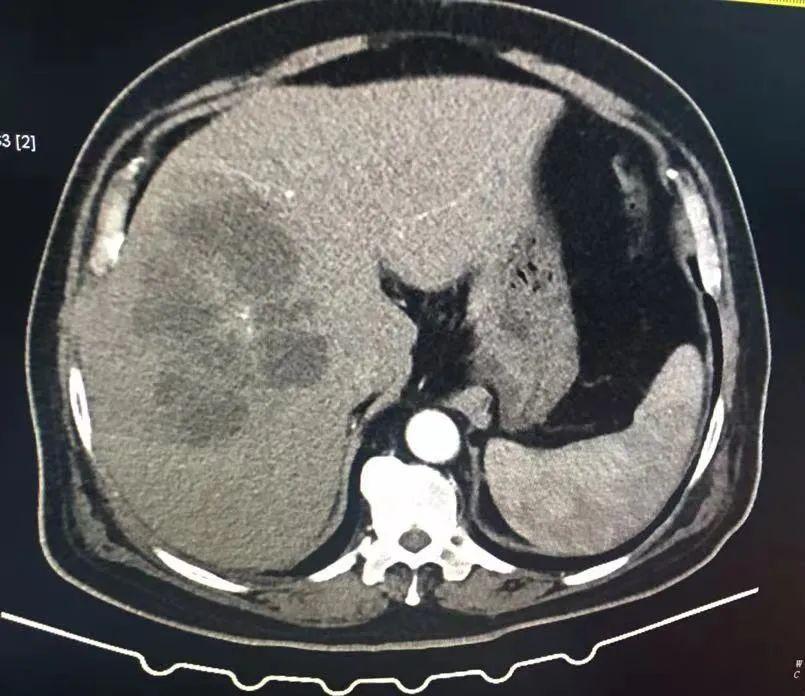

腹部CT: 肝右叶低密度灶,胆囊结石,建议增强CT;

腹部增强CT: 肝右叶多发肝脓肿、胆囊结石、腹主动脉硬化、食管裂孔疝、左肾囊肿。